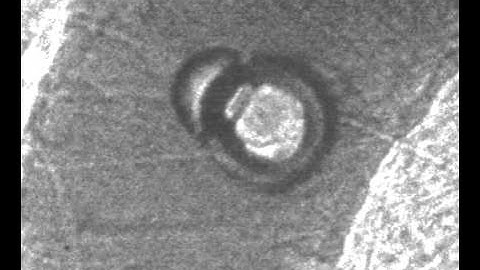

Microbubbles and cells interaction under high-speed microscopy